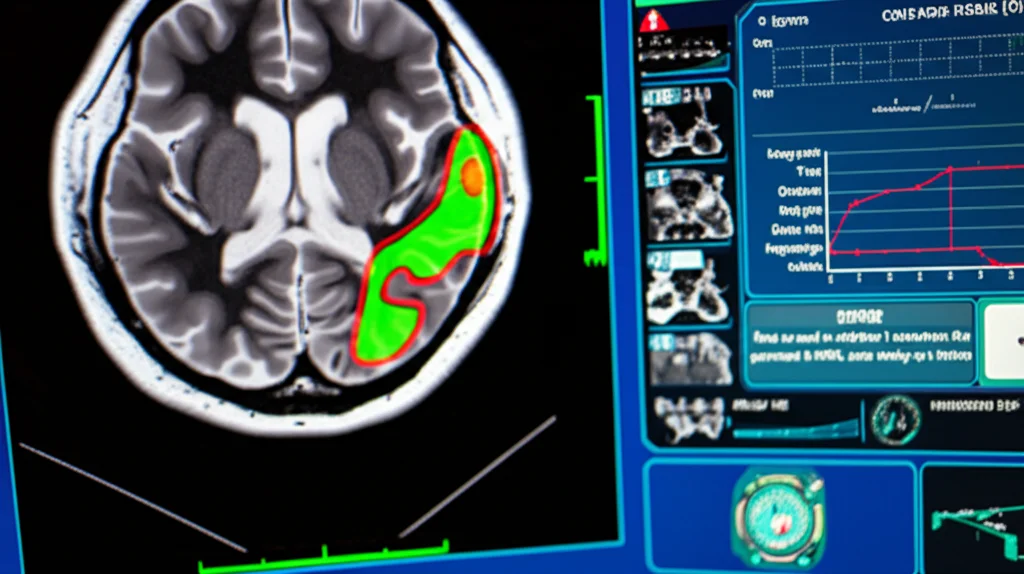

La segmentazione dei tumori cerebrali, cioè la capacità di delineare con precisione i confini del tumore separandolo dal tessuto sano nelle immagini mediche, è un passo fondamentale. Serve per capire dove si trova esattamente il tumore, quanto è grande, come cresce nel tempo e se ci sono anomalie nei tessuti circostanti. Pensate a quanto sia cruciale per pianificare un intervento chirurgico o una radioterapia: una mappa precisa è tutto!

Questo è cruciale per i tumori cerebrali, che possono avere forme irregolari, confini sfumati e presentarsi in modi molto diversi. Un meccanismo di attenzione di alto livello può, in teoria, catturare queste sottigliezze meglio dei sistemi precedenti, identificando pattern insoliti e comprendendo il contesto globale senza aggiungere un carico computazionale eccessivo.

Abbiamo anche notato che HLNet sembra essere particolarmente bravo a identificare aree tumorali che altri modelli faticavano a vedere, specialmente quelle più piccole o con confini meno definiti. Questo suggerisce che l’attenzione di alto livello sta davvero aiutando a catturare dettagli cruciali.